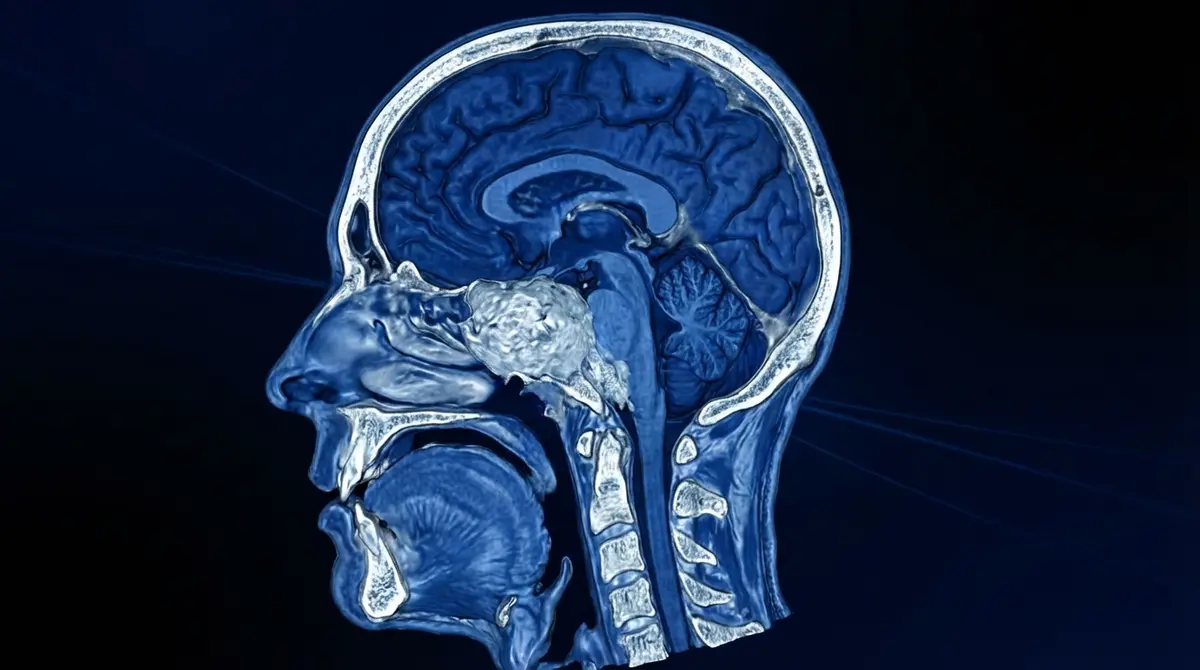

Cirurgia para remover um cordoma, tumor raro que nasce nas vértebras ou na base do crânio (clivus — osso na parte central da cabeça, atrás da nasofaringe). Este tumor cresce lentamente, mas pode comprimir o tronco encefálico, nervos cranianos e estruturas vitais, causando sintomas graves.

1️⃣ Planejamento: Imagem detalhada (RM e TC) para mapear relação com artérias vertebrais e tronco encefálico.

3️⃣ Exposição: Acesso ao clivus, identificação cuidadosa do tumor e estruturas vitais adjacentes (tronco, nervos, vasos).